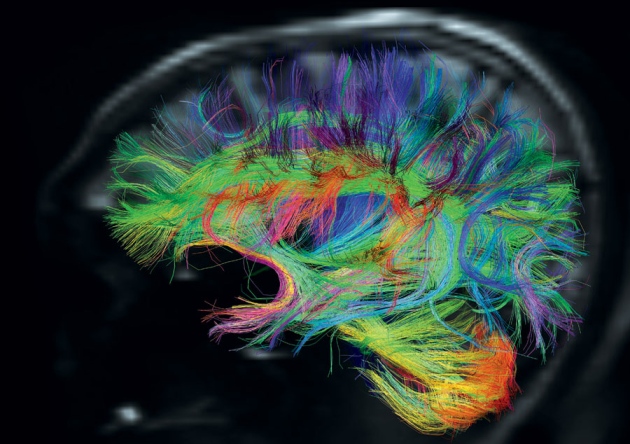

Коннектом мозга: визуализация связей и нейронных путей